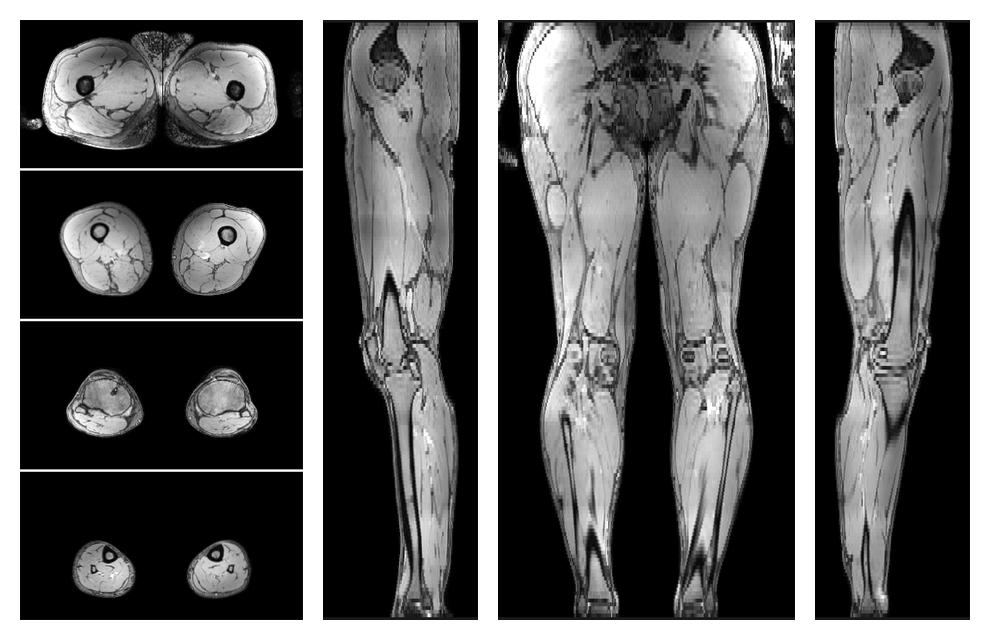

• Water only signal

The water part of the acquired multi-echo spin echo data.